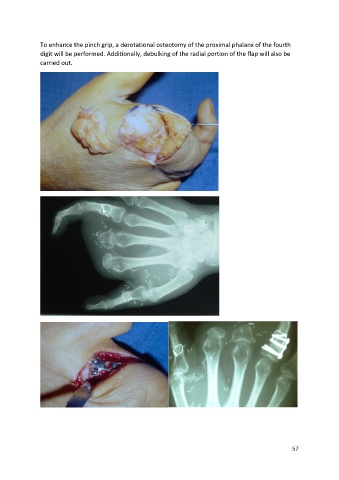

To enhance the pinch grip, a derotational osteotomy of the proximal phalanx of the fourth

digit will be performed. Additionally, debulking of the radial portion of the flap will also be

carried out.